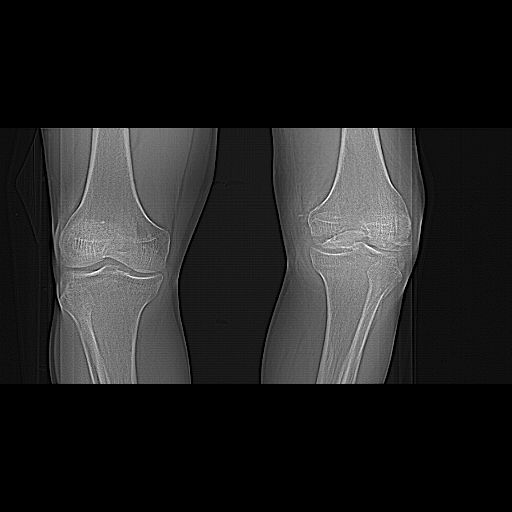

Before the CT and MRI era, we were treating the fractures with study of the Xrays alone. Such fractures with skeletal traction followed by non wtbearing mobilisation used to yield a fairly good range of movements. The CT gives a real ghastly picture of not so bad looking plain Xrays. I think this case needs traction to start with to correct the flexion deformity which probably will be achieved in 2 weeks time or less. We can then reassess the case with fresh Xrays. If possible one should try and fix the fragments to get some alignment. But the fixation should be stable enough to be able to mobilise the joint. Otherwise the traction can be continued for another 2 weeks to make the fracture sticky and then mobilise. We could get about 70 to 80* movements in spite of such communition. I am enclosing an Xray of a patient who is walking independantly and has 0 to 80* movemnts of the knee for the last one year

This is a coronal split in the femoral condyle and is a rare injury. Please see attachment for ORIF result